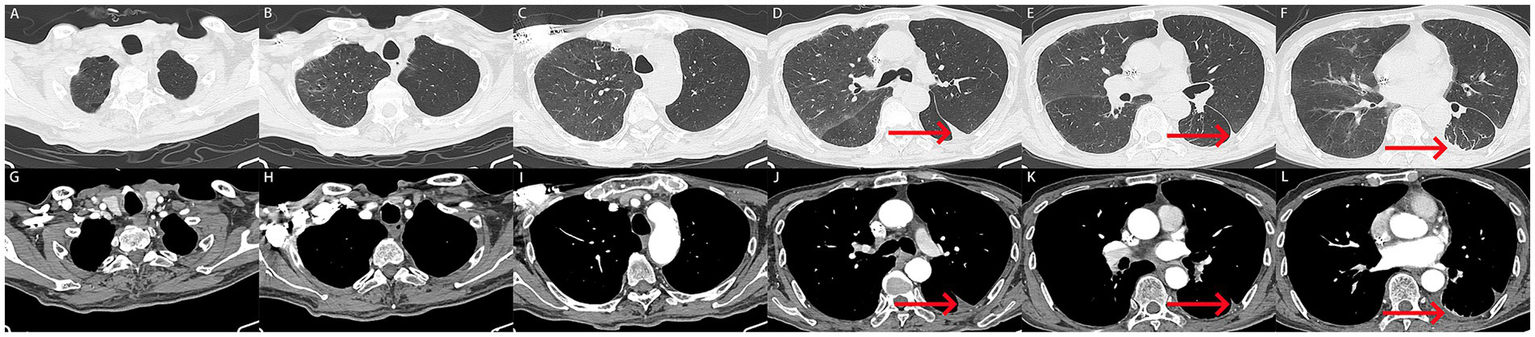

Following 5 days of treatment, the patient’s chest drain ceased to discharge hemorrhagic pleural effusion, and there was a significant improvement in the patient’s dyspnea, along with the normalization of coagulation function (Table 1). To rule out the possibility of pulmonary and pleural tumors, the patient subsequently underwent contrast-enhanced CT. The results indicated a marked reduction in hemothorax, improvement in atelectasis compared to previous findings, and no significant tumor-related manifestations in the lungs and pleura (Figures 3A–L). Consequently, the chest drain was removed, and the patient was discharged without complications (The timeline of key events is shown in Supplementary Figure S1). Fortunately, a follow-up CT scan 3 months later (November 12, 2024) revealed good re-expansion of the left lung and no recurrence of hemothorax (Figures 4A–L).

Figure 3

(A–L) After treatment, the patient underwent follow-up computed tomography imaging. (A–L) Computed tomography showed a marked reduction in hemothorax, with only a few pleural effusions in the left lung (red arrow). Atelectasis was improved, and no tumor related abnormalities were found in the lungs and pleura.

Figure 4

(A–L) 3 months later, the patient underwent follow-up computed tomography with no recurrent pleural effusion observed.